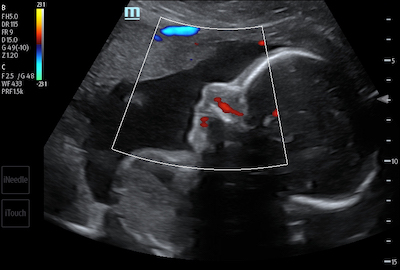

- Obstetrics – CDI is typically used in fetal monitoring from conception to delivery. It is used to detect the heartbeat of a fetus, blood flow in the umbilical cord, perfusion of the placenta, and helps to assist with prenatal care.

Color Doppler and Glazing Flow of Umbilical Vessels

Color Doppler Imaging of Fetal Breathing